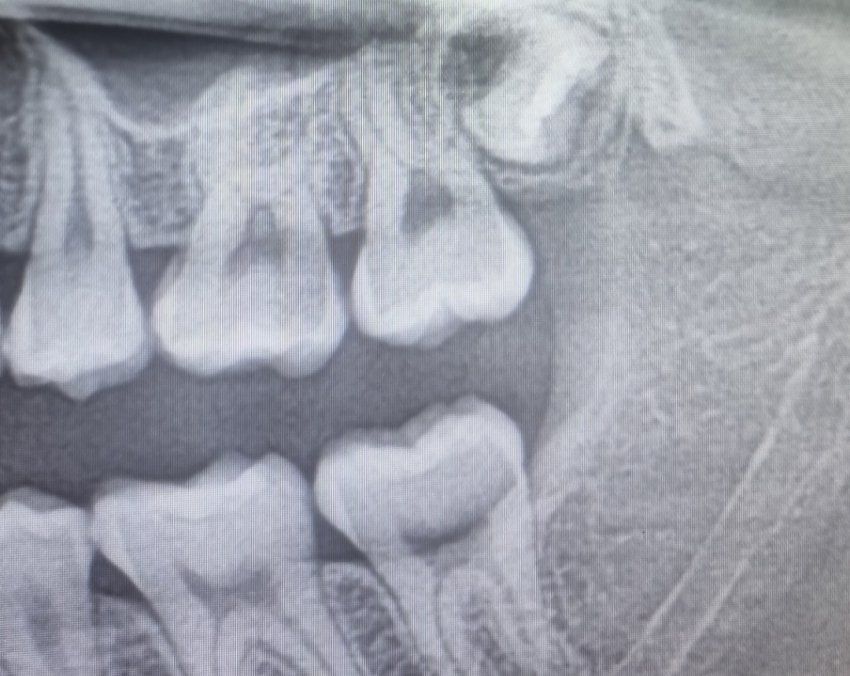

2달전에 찾은 제 사랑니 어떻게 하는게 좋을까요?

현재 예비 고3이고 사진은 2달전 치과에서 찍은 사진 입니다.

지금동안 사랑니가 나온다는 15세 이후로도 사랑니로 문제는 커녕 자라나는 사랑니도 없고 그래서 사랑니 4개 전부 없던 아빠처럼 저도 그냥 선천적으로 사랑니가 없는줄 알았지만

2달 전에 치과에서 왼쪽 상부에 아직 뿌리도 안자란 사랑니 1개를 발견 했습니다.

아직 이 왼쪽 상부 외에 사랑니는 없습니다

찾아보니 자라는 방향이 썩 좋은방향이 아닌거같고 해서 뿌리가 다 자라기 전에 뽑는게 좋을까 생각 해봤지만

• 1번 째 사진